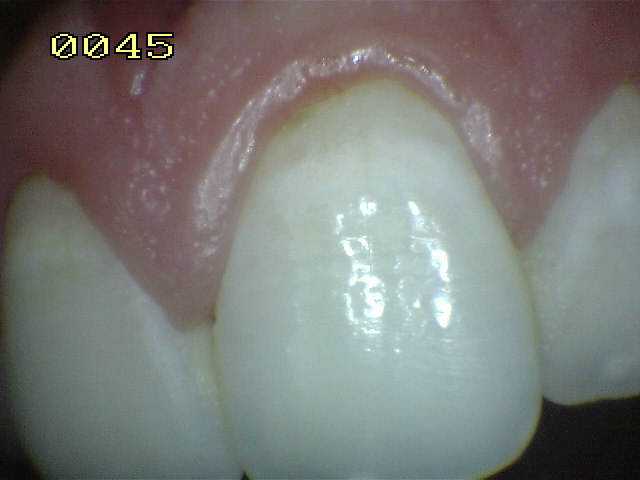

Encía inflamada |

Encía levemente inflamada con un

componente fibroso. Observe el borde gingival con aspecto

liso, turgente y brillante de color rojo |